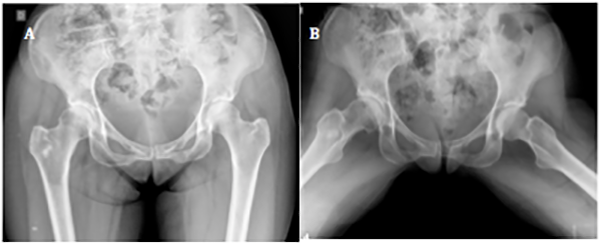

Se detectaron seis fallas (14.6%): dos casos progresaron a reemplazo total de cadera a los nueve y catorce meses postoperatorios (fig. 4), y cuatro presentaban síntomas persistentes luego de los nueve meses de la cirugía, los cuales, a la fecha, no requirieron de un procedimiento adicional.

Figura 4: Paciente femenina, cincuenta y siete años. A) Rx frente de ambas caderas, se observa esclerosis subcondral acentuada y signo de cross-over. B) Rx perfil de ambas caderas. Se visualiza el aplanamiento de la transición cabeza-cuello en ambos fémures. C) Rx ambas caderas, frente. Evolución a los tres meses postoperatorios. Se observa pinzamiento de la luz articular de cadera derecha. D) En la radiografía de perfil se constata una buena resección del CAM y del quiste de impacto en cabeza femoral, con progresión de la artrosis. E) Rx de ambas caderas, frente. A los seis meses de la cirugía se presenta a la consulta con coxartrosis polar superior. F) En el perfil se puede observar luz articular colapsada en el borde superoexterno de cadera derecha. G) Rx frente de ambas caderas. A los nueve meses de evolución se realizó la artroplastia total de cadera derecha.